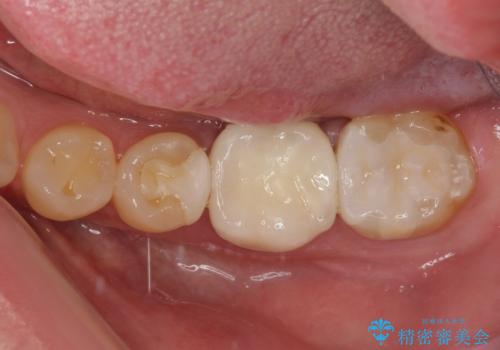

奥歯は虫歯が放置されていましたが、特に症状はなく歯髄の状態も正常でした。

前歯、奥歯ともにオールセラミッククラウンやセラミックインレーにて治療を行うこととしました。